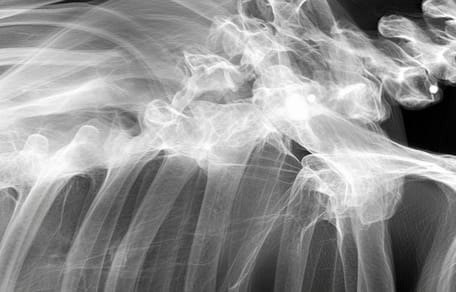

A dog's X-ray

A few years into their happy life together, Momo's owner got a nasty shock during a visit to the vet. He had taken her for a simple X-ray because she was starting to have trouble getting around. A silence fell over the consulting room as the vet explained that Momo had likely endured a very difficult and violent past. The X-ray suggested she had probably been used for mass breeding. But that wasn't all. The dog, who also suffered from arthritis and hip dysplasia, was hiding another secret.

A terrible secret

The vet soon discovered that Momo had been riddled with bullets. One of them had passed dangerously close to her spine. Fortunately, none of the bullets had a lasting impact on her life. As reported by Newsweek, this brave dog is now living the life she always dreamed of.